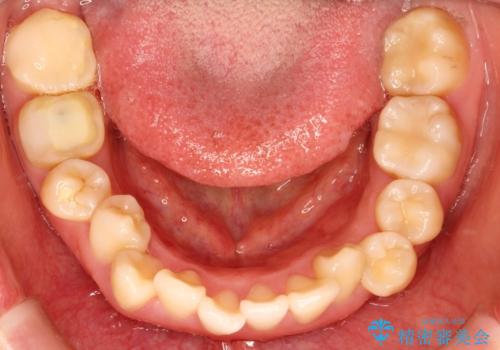

上下の歯のガタガタ ワイヤーでの抜歯矯正で整った歯並びへ

- 上下の歯のガタガタを治したいとのことで来院されました。

ガタガタが重度の方は抜歯が必要となることが多いです。